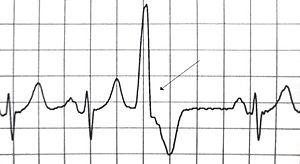

| A premature ventricular contraction marked by the arrow. | |

A premature heart beat is a heart rhythm disorder corresponding to a premature contraction of one of the chambers of the heart. Premature heart beats come in two different types, premature atrial contractions and premature ventricular contractions. Often they cause no symptoms but may present with fluttering in the chest or a skipped beat. Typically have no long term complications.

Premature heart beats can be asymptomatic (the patient does not complain about anything). The subject may experience palpitations, a feeling of cardiac "pause". Taking (prolonged) pulse may result in a rhythm that seems irregular. Electrocardiography and laser Doppler imaging[2] allow to visualize Premature heart beats. From their appearance, their location can be assessed. The Holter monitor allows to quantify them, to specify their characteristics and their repetition.